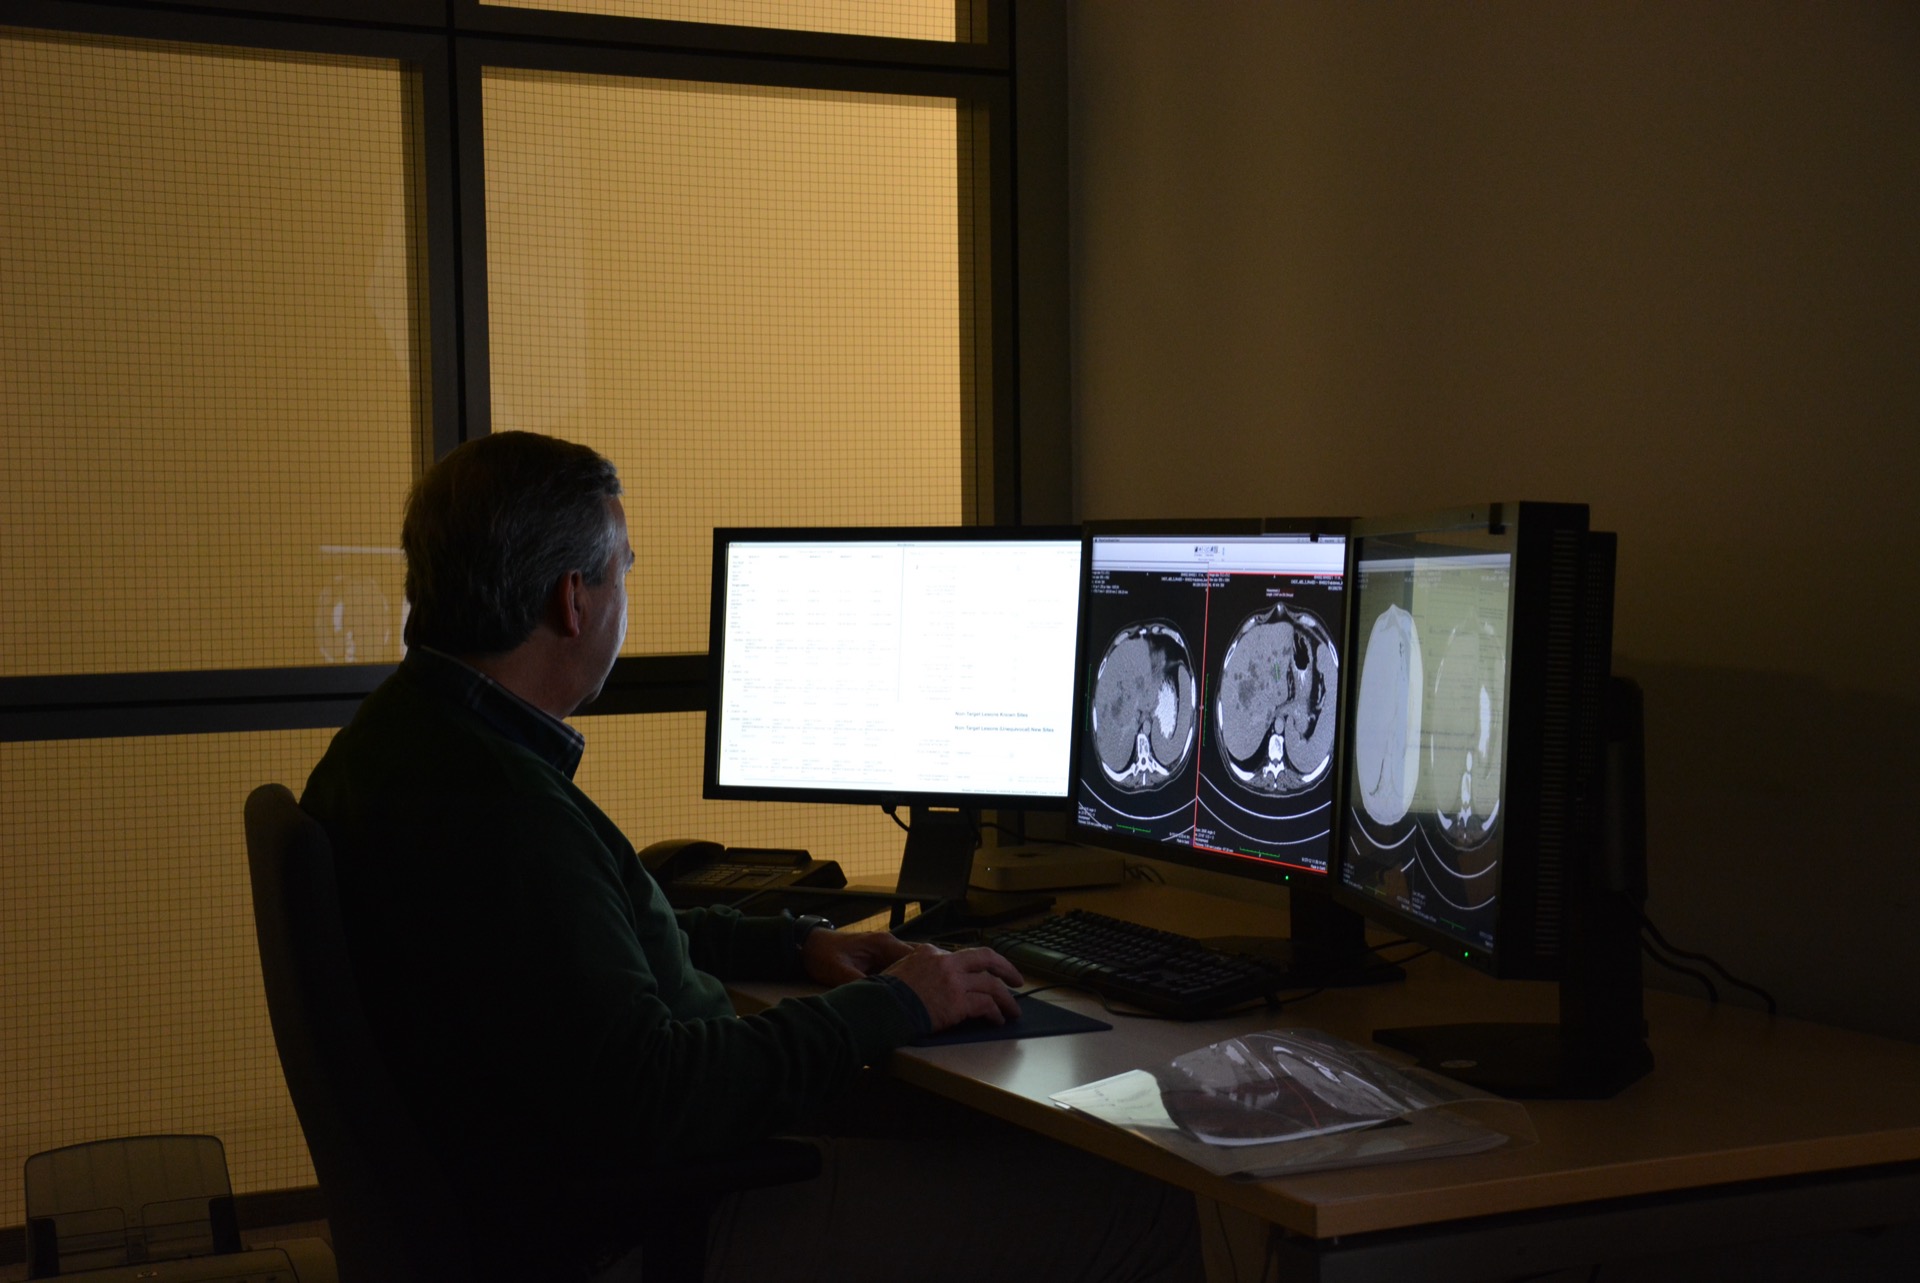

Imaging protocol, site qualification, DICOM logistics, and independent reads are managed by the same team running your trial — not contracted out to a separate imaging vendor. Most sponsors coordinate a CRO and an imaging core lab independently. We are both — one team, one point of accountability, from protocol to final read.

From imaging charter and site qualification through DICOM image collection, quality control, and blinded reads to the final results dataset — we manage every imaging step with the rigour that regulatory submissions demand. Response criteria covered include RECIST 1.1, iRECIST, PERCIST, and study-specific frameworks.

ERICA is our proprietary, fully validated imaging platform — purpose-built for the demands of clinical trials. It covers DICOM image storage, technical and medical quality control, and independent blinded reads in a single, regulatory-compliant environment.

Every project-specific configuration is separately validated. No general-purpose software adapted for clinical use — a system designed from the ground up for this work.